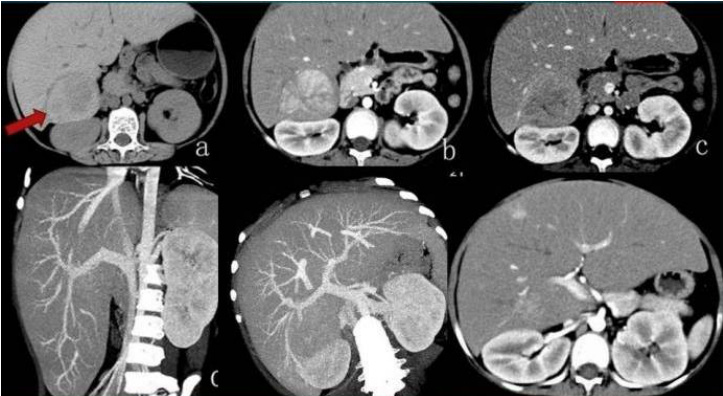

图 1 肝糖原累积病(GSD)